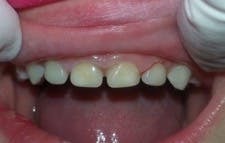

I apply a self-etching bonding agent, light cure, and fill the strip crowns with Activa BioActive-Restorative. I usually seat the central incisor crowns first, light cure, and then seat the laterals. I remove the strip crowns with an explorer, and very little finishing is required. I use Sof-Lex disks (3M) for the incisal and a fluted carbide at the gingival margin if necessary.

This case took less than 20 minutes and looks great (figure 4). Leigh is pleased with his smile and asked if we could fix more teeth. No anesthesia, no tears, and a happy child looking forward to his next visit to the dentist!